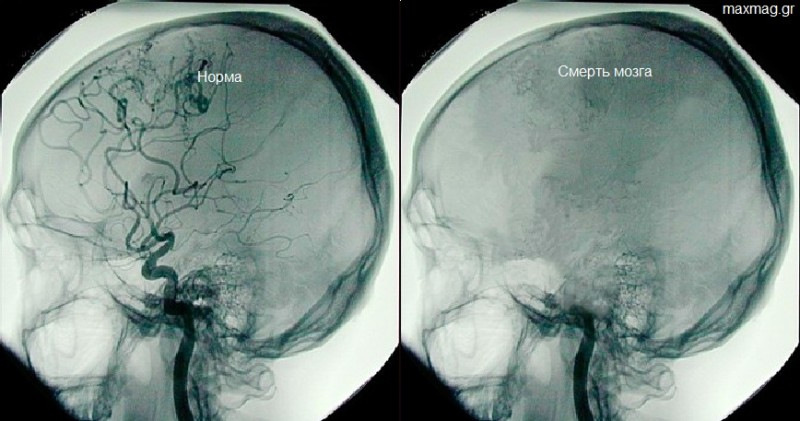

Через три дня врачи диагностировали смерть, но по настоянию родственников к телу подключили аппаратуру внутривенного питания, депо антибиотиков, гормонов тонуса и препаратов для стабилизации состава крови. Отдельный вопрос — организация передачи любви неродившимся детям. Для этого родственники и персонал стали посещать палату по графику, петь песни и разговаривать с эмбрионами, которые развивались в лоне мертвой матери.

Через три дня врачи диагностировали смерть, но по настоянию родственников к телу подключили аппаратуру внутривенного питания, депо антибиотиков, гормонов тонуса и препаратов для стабилизации состава крови.